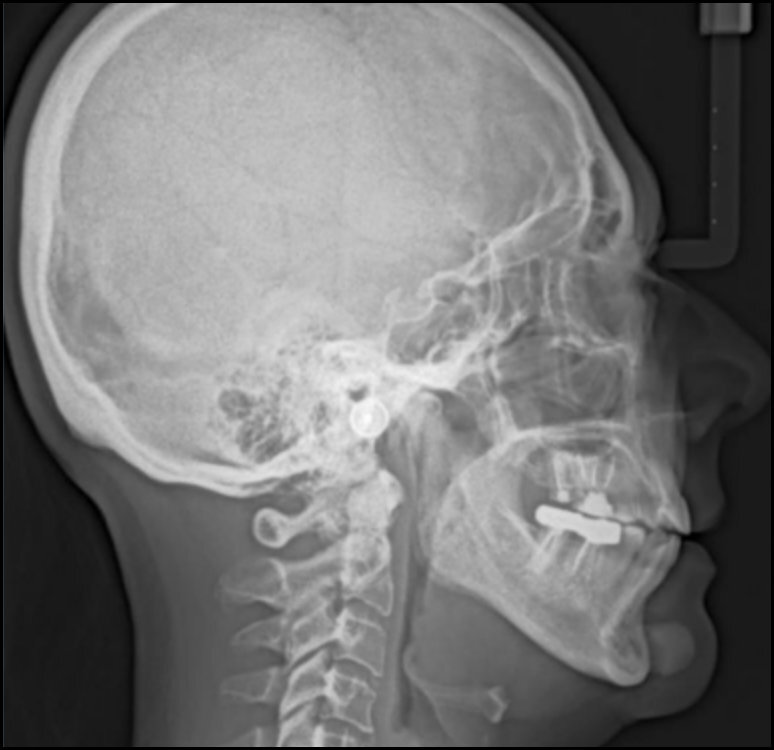

A high-quality panoramic x-ray is a good starting point when looking for the presence of any TMD or other pathology. While it is not a highly definitive indicator specifically of actual TMJ pathology, a normal appearing panoramic x-ray can aid the process of elimination of other potential conditions. See Figure 1. Panoramic x-rays are typically more readily available and less costly than the more sophisticated MRI or CT scans. A clear panoramic x-ray can also point to the need for a more definitive image or indicate that it is probably not needed.

The development of tomography created a more linear x-ray image with less ionizing radiation. The addition of a computer added the possibility of allowing the viewer to adjust the slices and consequently the views. The relatively recent development of the newer Cone Beam Computed Tomography machines has reduced the radiation exposure 96 % lower than for previous medical CT scanning. It has also lowered the cost of obtaining the images. Although the CBCT is not accurate for measuring bone density, the acquisition of 3-Dimensional anatomical datasets of voxels has been very useful in oral surgery, endodontics, orthodontics, implantology, and for 3-D imaging of the TMJ. See Figure 3.

More recently the pharyngeal airway space of patients with sleep disorders has frequently been imaged. See Figure 4.